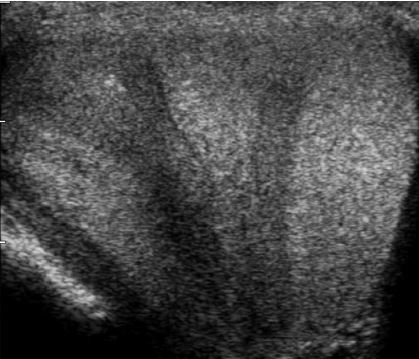

Focal testicular atrophy

• Focal hypoechoic striations and bandlike regions radiating from the periphery of the testis toward the mediastinum.

• Due to focal tubular atrophy and fibrosis